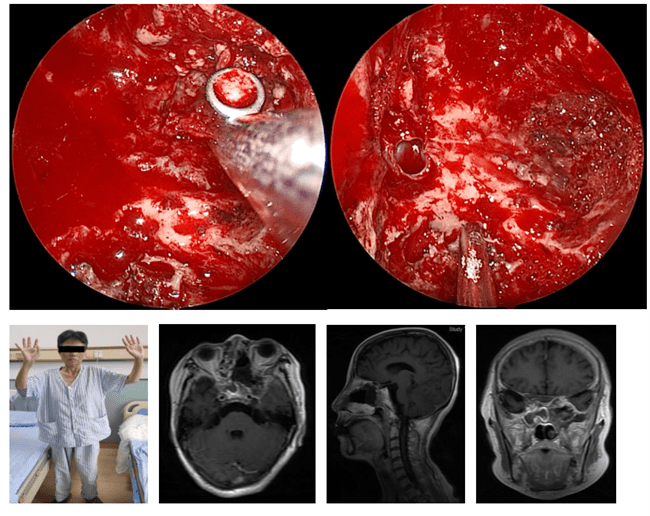

术前神经外科王宁教授团队与耳鼻喉科李慧军教授团队一同制定了周密的手术计划 , 先由耳鼻喉科王启威副主任医师内镜下行筛窦、上颌窦开放 , 并切除侵及相关区域病变 。 然后神经外科王宁教授及邵奇主治医生内镜下进行了侵及翼腭窝、蝶窦、海绵窦病变的切除 。 术后进行磁共振检查显示肿瘤全切 , 困扰折磨患者已久的典型三叉神经痛症状消失 , 恢复满意出院 。

文章图片

患者术后进行磁共振检查显示肿瘤全切 。 哈医大医院 供图